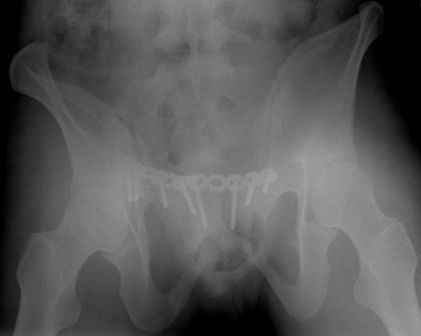

Re: перелом таза

Серия до- и послеоперационных снимков этой пациентки. Хотя бы post factum обсудить. Не знаю, что можно сделать с задними отделами стержневым аппаратом, но три крепких парня открытым путем с помощью "волшебных" слов еле-еле смогли отрепонировать - сзади все было очень ригидно!